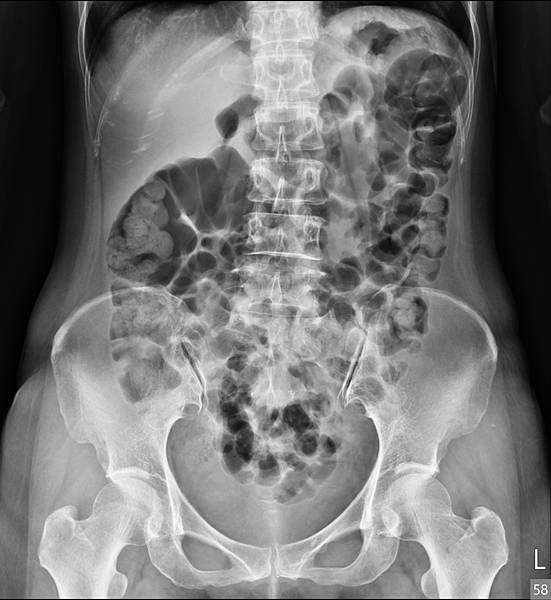

下面的病人,80歲女性,長期胃食道逆流,每半年做一次胃鏡(診斷GERD LA Gr A),斷斷續續吃PPI兩三年。GERD LA Gr A這種診斷是假的胃食道逆流,方便醫師開PPI而已。照一張X光片,真實的情況如下:

她的問題出在腸道產氣細菌製造出來的腸氣影響(抑制)大腸蠕動,大腸蠕動慢,吸收水分多,造成升結腸的糞便因水分吸收過多而呈羊屎狀。解決方式是「清腸+益生菌」,兩週後的X光片如下: